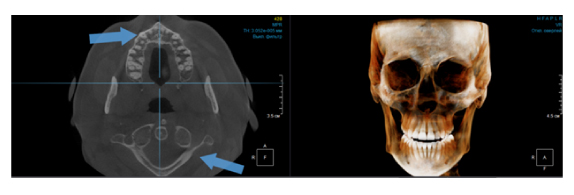

Когда мы отправляем пациента на проведение рентгенологического исследования, то подвергаем его определенному риску. Именно это нужно осознавать, так как в радиологии нет минимально безопасной дозы, поэтому любое назначение должно быть обоснованным. В связи с этим поле обзора является достаточно принципиальным параметром. Если вы врач-терапевт, занимающийся эндодонтией или ортопед, который решил оценить состояние зубов перед протезированием, то вы должны понимать, что проведение исследования с полем обзора 10x10 см будет гораздо информативнее нежели большие снимки (18x16 см и выше). В первую очередь это связано с размером вокселя, о нём я напишу чуть ниже, а второе это то, что вам придется увеличивать изображение по каждому корневому каналу, и от этого вы будете терять в качестве снимка (рис. 1). И ситуация наоборот, если вы ортодонт, то чтобы использовать весь диагностический потенциал, а также возможность загрузить данные для расчёта 3D цефалометрии, то вам нужны снимки, захватывающие весь лицевой отдел черепа. Таким образом, дентальный томограф должен обладать возможностью проведения исследований с разным FOV, обеспечивая нужды всех специалистов. Если ваша клиника базируется на терапевтическом, хирургическом и ортопедическом приёме, то на мой взгляд, можно рассмотреть дентальные томографы с полем обзора 10x10 см или 16x10 см. Последний больше актуален для тех, кто работает с ВНЧС, так как антропометрически в 16 см даже у брахицефалов сустав должен попадать.  Если в клинике есть ортодонтическое направление, функциональная стоматология, ЛОР-практика или ЧЛХ, то, безусловно, вышепредставленные снимки не будут отражать всех данных, которые необходимы для диагностики и планирования лечения. Здесь лучше рассмотреть конусно-лучевые компьютерные томографы с зоной сканирования 18x16 или 20x20 см. Особо стоит отметить понятие «сшивки». Есть дентальные томографы, которые делают один цельный снимок размерами, которые описаны выше, а есть аппараты, которым нужно провести две экспозиции и сшить изображения вместе, чтобы получился необходимый объём исследования. Как правило, вторые томографы чуть дешевле, но всё зависит от того, насколько вам нужна максимальная точность исследования. Если при сшивке челюсти и зубы, как правило, совмещаются практически идеально, то на уровне позвоночного столба происходит наслоение тканей и от него уже не избавиться (рис. 2). Второй отрицательный момент – это износ оборудования, логично, что он будет быстрее, так что экономия средств — это ещё спорный вопрос.

Рис. 1. Представлены два исследования (10x10 см и 20x20 см). На обоих изображениях хорошо видна канально-корневая система зубов, но, если масштабировать второе исследование, то качество неминуемо снизится, как и диагностическая эндодонтическая эффективность.

Рис. 2. Левый снимок представлен исследованием 20x20 см единым изображением. Стрелками показаны чёткость канально-корневой системы зуба, а также позвоночника. Правый снимок представлен исследованием 16x15 см с функцией сшивки. Стрелками обозначены чёткость зуба, но двойной контур позвоночника.